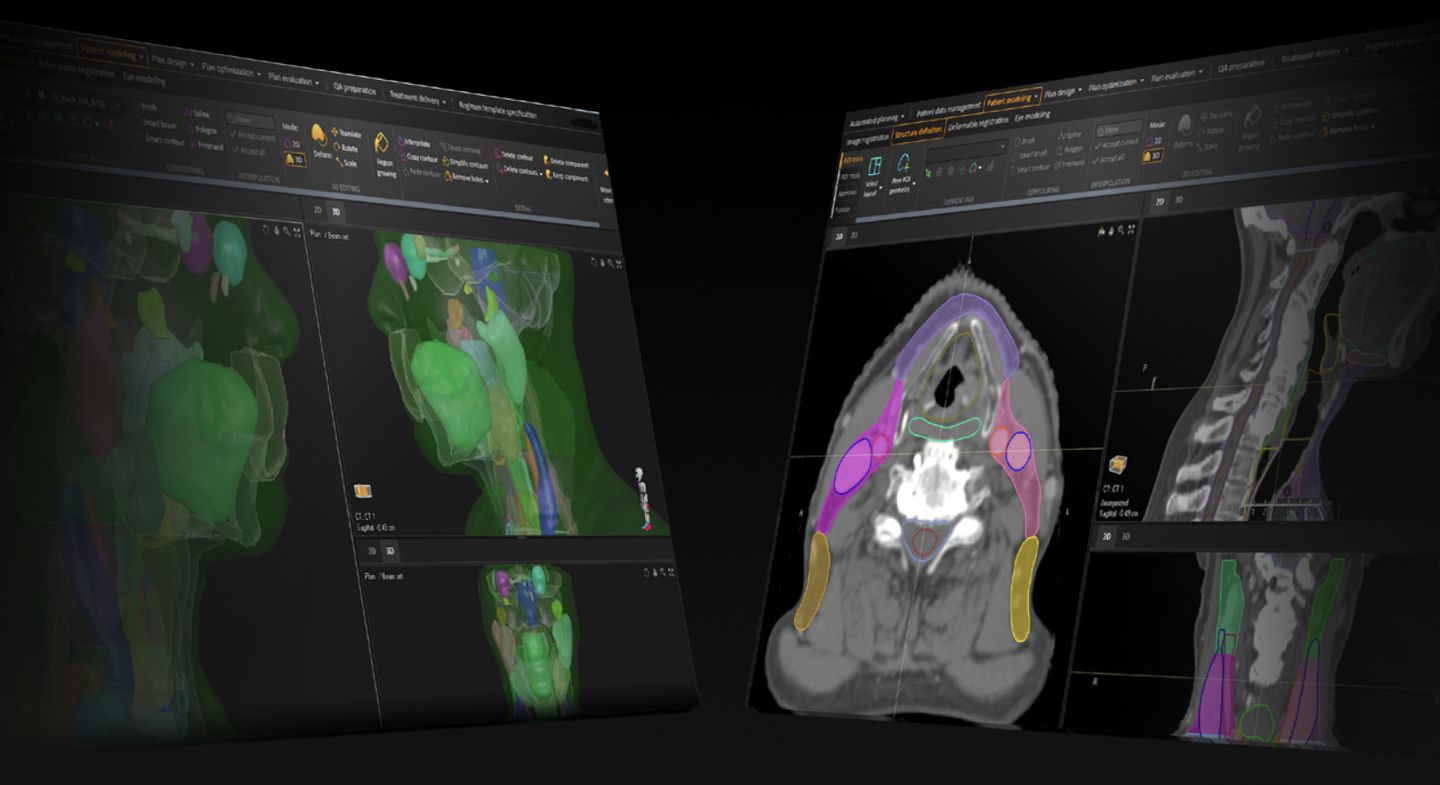

At RaySearch Laboratories, we transform energy into intelligence — enabling clinicians to harness protons, carbon ions, BNCT, and photons with greater precision, control, and adaptability.

Radiotherapy software has always been our core technology. Through advanced optimization algorithms and numerous lines of codes, our solutions shape emergent therapeutical energy into smarter, safer cancer treatments.